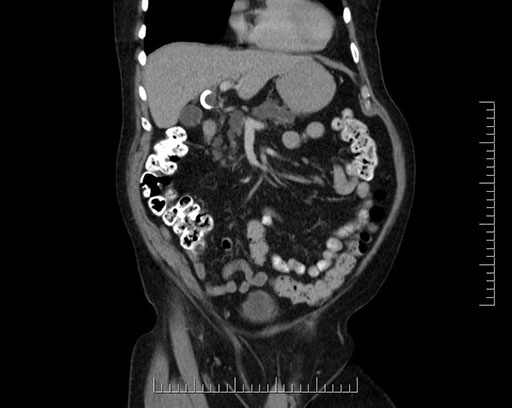

Imaging Analysis

Look through the patient's CT scan to identify any areas of concern for the necessary procedure.

Based on your CT findings, which issue(s) would give reason for "planned slowing down moment(s)" in this case?

Considering a standard Whipple procedure, what step(s) of the operation would you do differently in this case?